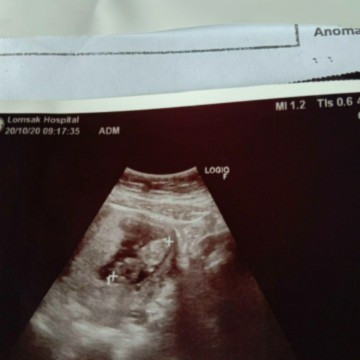

13w5d เจอตัวและเสียงหัวใจเต้นแล้วจ้า ก่อนหน้านี้ซาวไม่เจอเสียใจและกังวลมาก

ตอน 6 วีคซาวไม่เจอตัวน้อง หมอแจ้งว่าเราอาจจะไข่ฝ่อหรือไข่แตก ตอนหมอพูดเราเสียใจมาก เศร้าและเครียดอยู่เป็นเดือนเลยคะ วันนี้กลับไปหาหมออีกรอบ 13w5d แล้วจ้า ตอนนี้เจอตัวน้องและเสียงหัวใจเต้นปกติดิ้นเก่งและแข็งแรงดีคะ